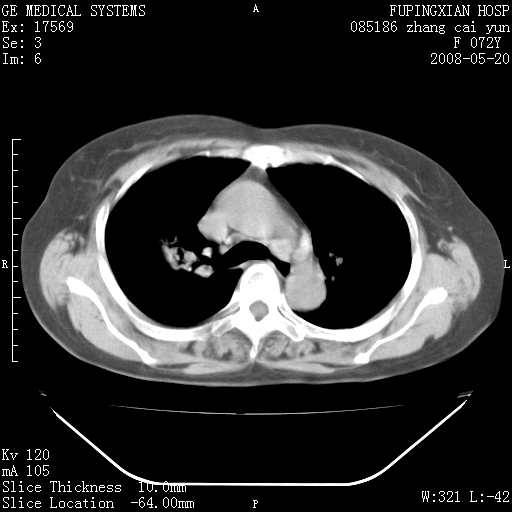

标题: CT13542:发热,咳嗽数日,经抗菌素治疗好转,请大家看排除 [打印本页]

标题: CT13542:发热,咳嗽数日,经抗菌素治疗好转,请大家看排除

上叶支气管略变窄并通畅,内壁光滑。考虑:单纯阻塞性肺炎!

右上叶支气管走行自然,未见明显管壁增厚等征像,另左主支气管起始部可见异常腔道向左侧延展左肺动脉干后方,与左下叶支气管相通,为左下叶支气管变异?

有节段性阻塞性肺炎与不张,近段支气管狭窄,周围散在肿大淋巴结影,以周围型肺癌可能性大,建议纤支镜检查。

右肺上叶实变影,内见支气管充气征,右上叶支气管通畅,肺门区未见软组织密度影,抗炎治疗有效,考虑炎症,建议继续抗炎治疗复查。

右上肺实变,间内有支气管充气征,考虑炎症,建议抗炎后复查